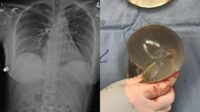

Viral Kisah Wanita Selamat dari Tembakan gegara Pelurunya Nyangkut di Payudara

Jakarta – Viral kisah seorang wanita terselamatkan dari tembakan misterius karena pelurunya menyangkut di implan Baca selengkapnya…